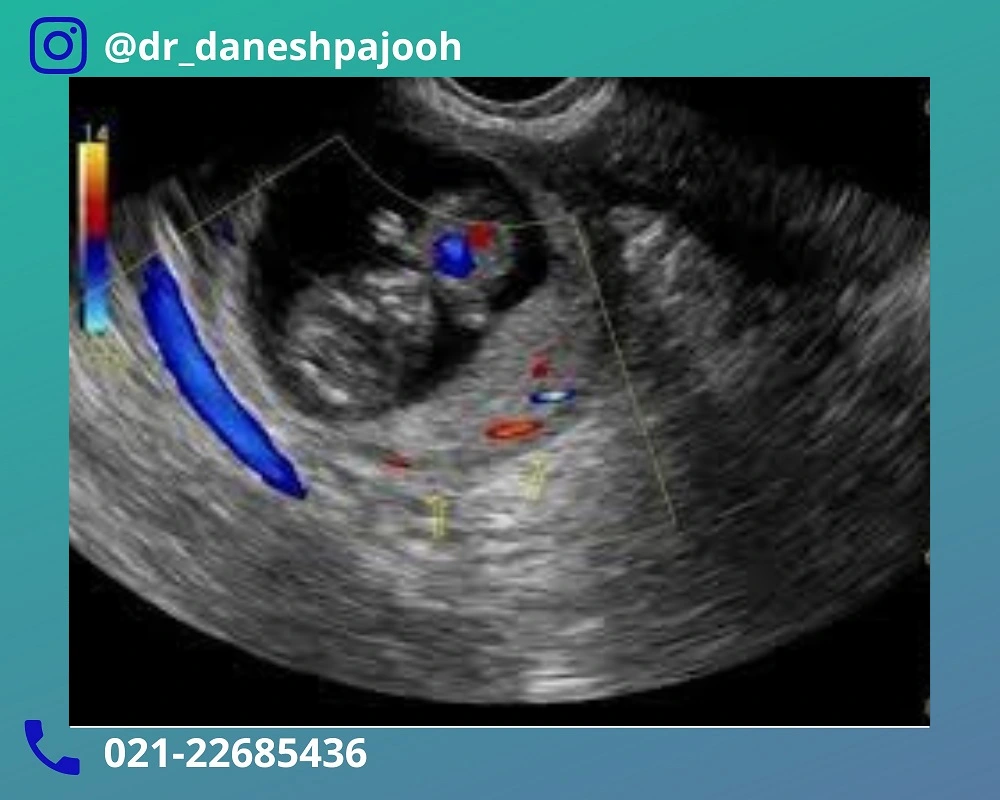

کیست درموئید اواریان در بارداری برخلاف بسیاری از کیست های عملکردی، خود به خود جذب نمی شود و اغلب ساختاری پیچیده دارد. این کیست ممکن است شامل بافت های متنوعی از جمله چربی، استخوان، دندان یا مو باشد. چنین کیستی در تصویربرداری سونوگرافیک الگوی خاصی ایجاد خواهد کرد. همین ویژگی ها موجب می شود که تشخیص آن نسبتا دقیق و قابل اعتماد باشد.

تشخیص کیست درموئید تخمدان در بارداری اغلب به صورت اتفاقی و در جریان سونوگرافی های روتین بارداری انجام می شود. بسیاری از زنان باردار هیچ علامتی ندارند. تنها در بررسی های تصویربرداری مشخص می شود که یک کیست تخمدان با ویژگی های خاص در یکی از تخمدان ها وجود دارد. ظاهر ناهمگون، وجود سایه های صوتی و اجزای چرب از جمله یافته هایی هستند که تشخیص کیست درموئید را به قطعیت می رساند.

در برخی موارد، برای تایید تشخیص کیست درموئید از سونوگرافی ترانس واژینال یا سونوگرافی شکمی با وضوح بالا استفاده می شود. در شرایط خاص و در صورت ابهام تشخیصی، تصویربرداری MRI بدون ماده حاجب نیز می تواند به تشخیص دقیق نوع کیست کمک کند؛ زیرا این روش برای جنین بی خطر تلقی می شود.